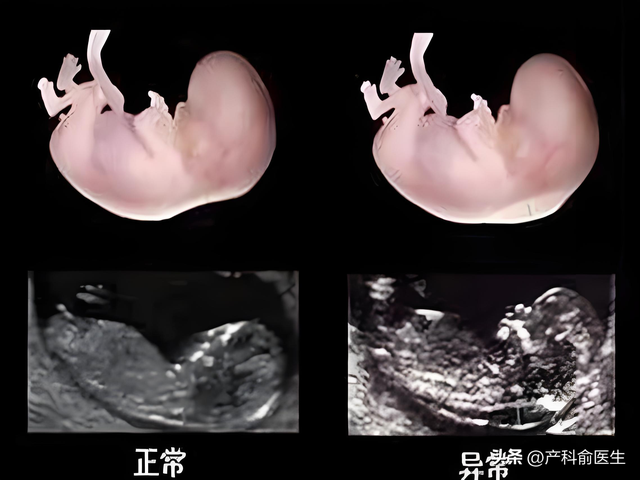

唐氏综合征筛查:NT增厚是染色体异常的重要预警信号;先天性心脏病提示:异常NT值可能反映胎儿心脏发育问题。

其他畸形排查:如骨骼系统异常、先天性膈疝等。

临床数据显示,NT检查结合血清学筛查(早唐),对唐氏综合征的检出率可达85%以上。这远比猜测性别更有意义。